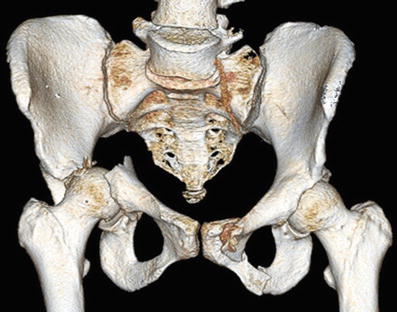

Three-dimensional surface-rendered images generated from CT data are helpful when planning the surgical treatment of a displaced acetabular fracture. In this example, the right-sided transverse acetabular fracture is seen to divide the joint into two separate halves. The caudal fragment is displaced medially from the intact and stable cranial portion, and the proximal femur remains in association with the displaced caudal fragment. The 3D image also demonstrates a left-sided sacroiliac joint disruption and pubic ramus fracture

This patient (previously seen in Fig. 3) had a right transverse acetabular fracture-dislocation as well as left pubic ramus fracture and SI joint disruption. The acetabular fracture was treated operatively using a posterior Kocher-Langenbeck exposure. The reduction was accomplished after cleaning the fracture surfaces and then clamping the transverse fracture. A cancellous lag screw was inserted percutaneously in the superior pubic ramus, and then two malleable plates were applied posteriorly to stabilize the transverse fracture. The SI joint injury and pubic ramus fracture were treated with closed reduction and then screw fixation. An initial iliosacral cancellous lag screw compressed the SI joint, and the subsequent fully threaded cancellous screw provided additional support. The acetabular lag screw, iliosacral screws, and the retrograde superior pubic ramus screw were all inserted percutaneously using biplanar fluoroscopic imaging